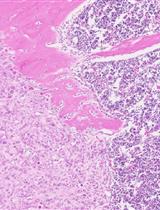

用胫骨肿瘤发生法测定骨转移瘤的生长

Measurement of Bone Metastatic Tumor Growth by a Tibial Tumorigenesis Assay

BZ Baotong Zhang

XL Xin Li

WQ Wei-Ping Qian

DW Daqing Wu

JD Jin-Tang Dong

4551 Views

Nov 20, 2021

Bone metastasis is a frequent and lethal complication of many cancer types (i.e., prostate cancer, breast cancer, and multiple myeloma), and a cure for bone metastasis remains elusive. To recapitulate the process of bone metastasis and understand how cancer cells metastasize to bone, intracardiac injection and intracaudal arterial animal models were developed. The intratibial injection animal model was established to investigate the communication between cancer cells and the bone microenvironment and to mimic the setting of prostate cancer patients with bone metastasis. Given that detailed protocols of intratibial injection and its quantitative analysis are still insufficient, in this protocol, we provide hands-on procedures for how to prepare cells, perform the tibial injection, monitor tibial tumor growth, and quantitatively evaluate the tibial tumors in pathological samples. This manuscript provides a ready-to-use experimental protocol for investigating cancer cell behaviors in bone and developing novel therapeutic strategies for bone metastatic cancer patients.